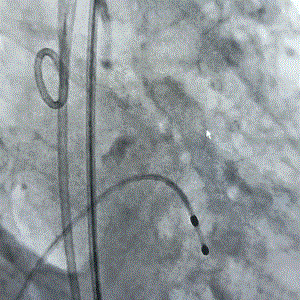

术前造影(见大量反流)                                   术后造影